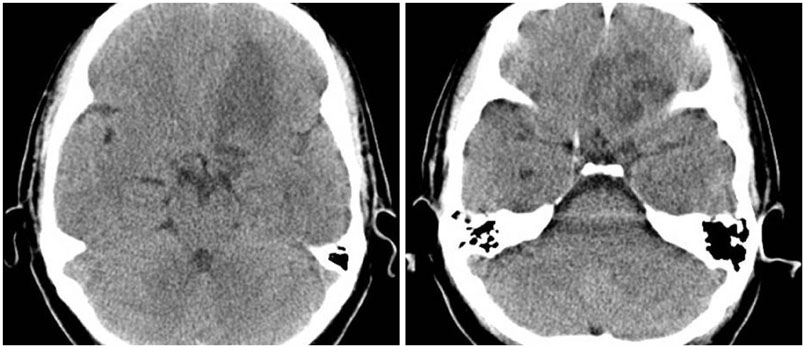

- The olfactory groove schwannoma is a quite rare tumor. We report a case of a 49-year-old woman with an olfactory groove schwannoma attached to the cribriform plate without olfactory dysfunction. She had no specific neurological symptoms other than a headache, and resection of the tumor showed it to be a schwannoma. About 19 months after the operation, a follow-up MRI showed no evidence of tumor recurrence. Surgical resection through subfrontal approach could be one of the curative modality in managing an olfactory groove schwannoma. An olfactory groove schwannoma should be considered in the differential diagnosis of anterior skull base tumors.